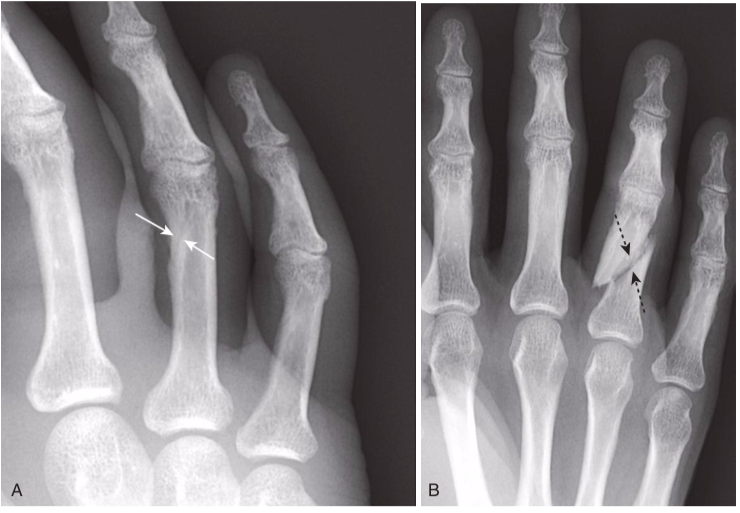

Nutrient canal versus fracture.

Fracture lines, when viewed in the correct orientation, tend to be “blacker”(more lucent) than other lines normally found in bones, such as nutrient canals. A,This is a nutrient canal (white arrows), whereas a true fracture is seen in another patient in (B)(dotted black arrows). Notice how the nutrient canal has a sclerotic (whiter) margin and is confined to the cortex, which is not the case with fracture lines that are darker and traverse the cortex and medullary cavity. The edges of a fracture tend to be jagged and rough.